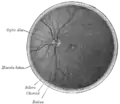

Interior of posterior half of bulb of left eye. The veins are darker in appearance than the arteries. (Central retinal artery visible but not labeled).